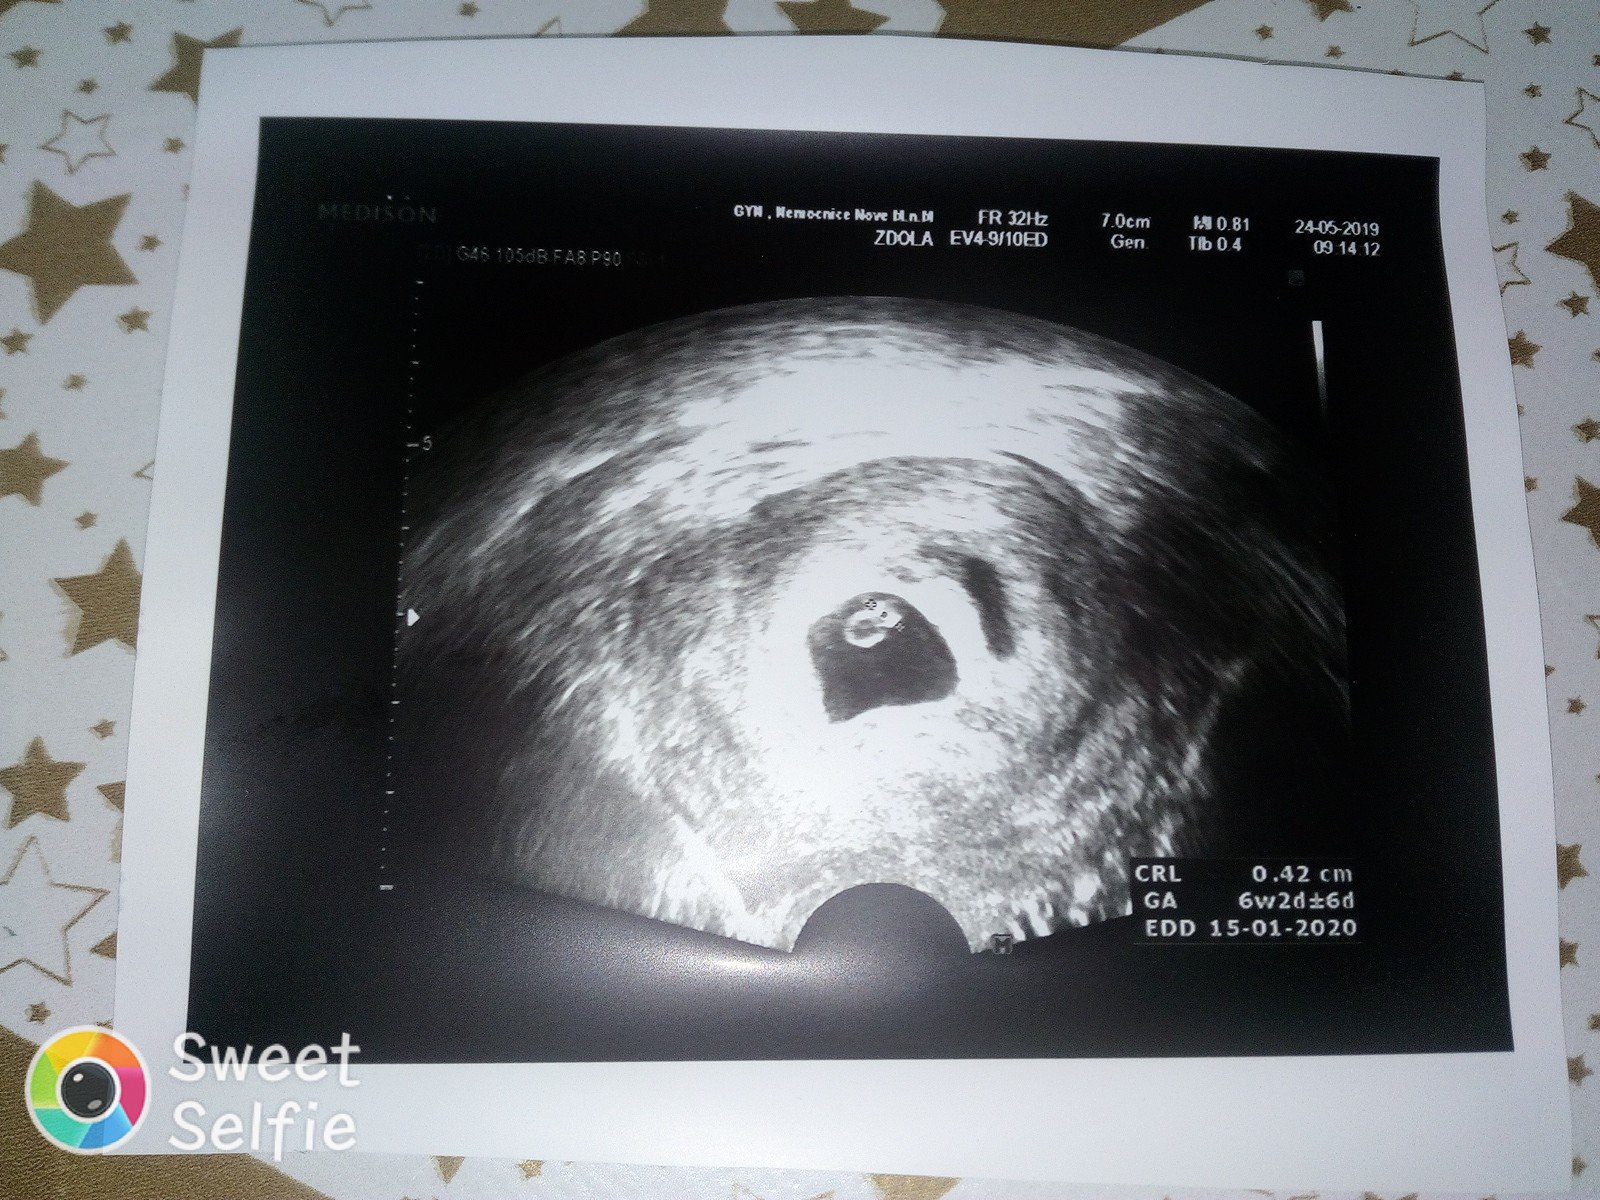

@hobbitka Já jsem v čekárně stála a jen se modlila: prosím ne dvojčata, jen ne dvojčata. Čekáme tedy jen jedno 😅